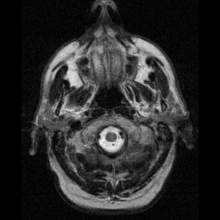

Neuroimaging

Neuroferritinopathy is most commonly diagnosed using MRI and other neuroimaging techniques.[1] MRIs help identify the iron deposits in the cerebellum, basal ganglia, and motor cortex common to neuroferritinopathy.[8] MRIs of affected individuals also show mild cerebellar and cerebral atrophy, or tissue breakdown, and gas cavity formation in the putamen.[8] Most importantly, the MRIs show misfolded ferritin proteins and iron deposits in the glial cells of the caudate, putamen, globus pallidus, cerebral cortex, thalamus, and purkinje cells, causing neuronal death in these areas.[8]